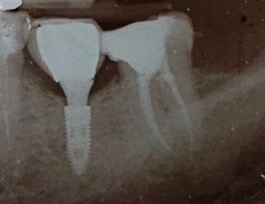

Conservare denti naturali più a lungo possibile è infatti molto importante poiché attorno alle radici esistono dei legamenti che ci permettono di percepire e modulare la forza quando mastichiamo qualcosa.

Un adeguata endondonzia serve per salvare quei denti che altrimenti sarebbero destinati ad essere estratti. Quando un dente viene devitalizzato viene privato della sua irrorazione sanguigna e del nutrimento, rendendo la sua struttura più “vetrosa” quindi più fragile e soggetta a fratture. Per questo motivo è consigliabile nella maggior parte dei casi capsulare i denti una volta che hanno perso la loro vitalità.